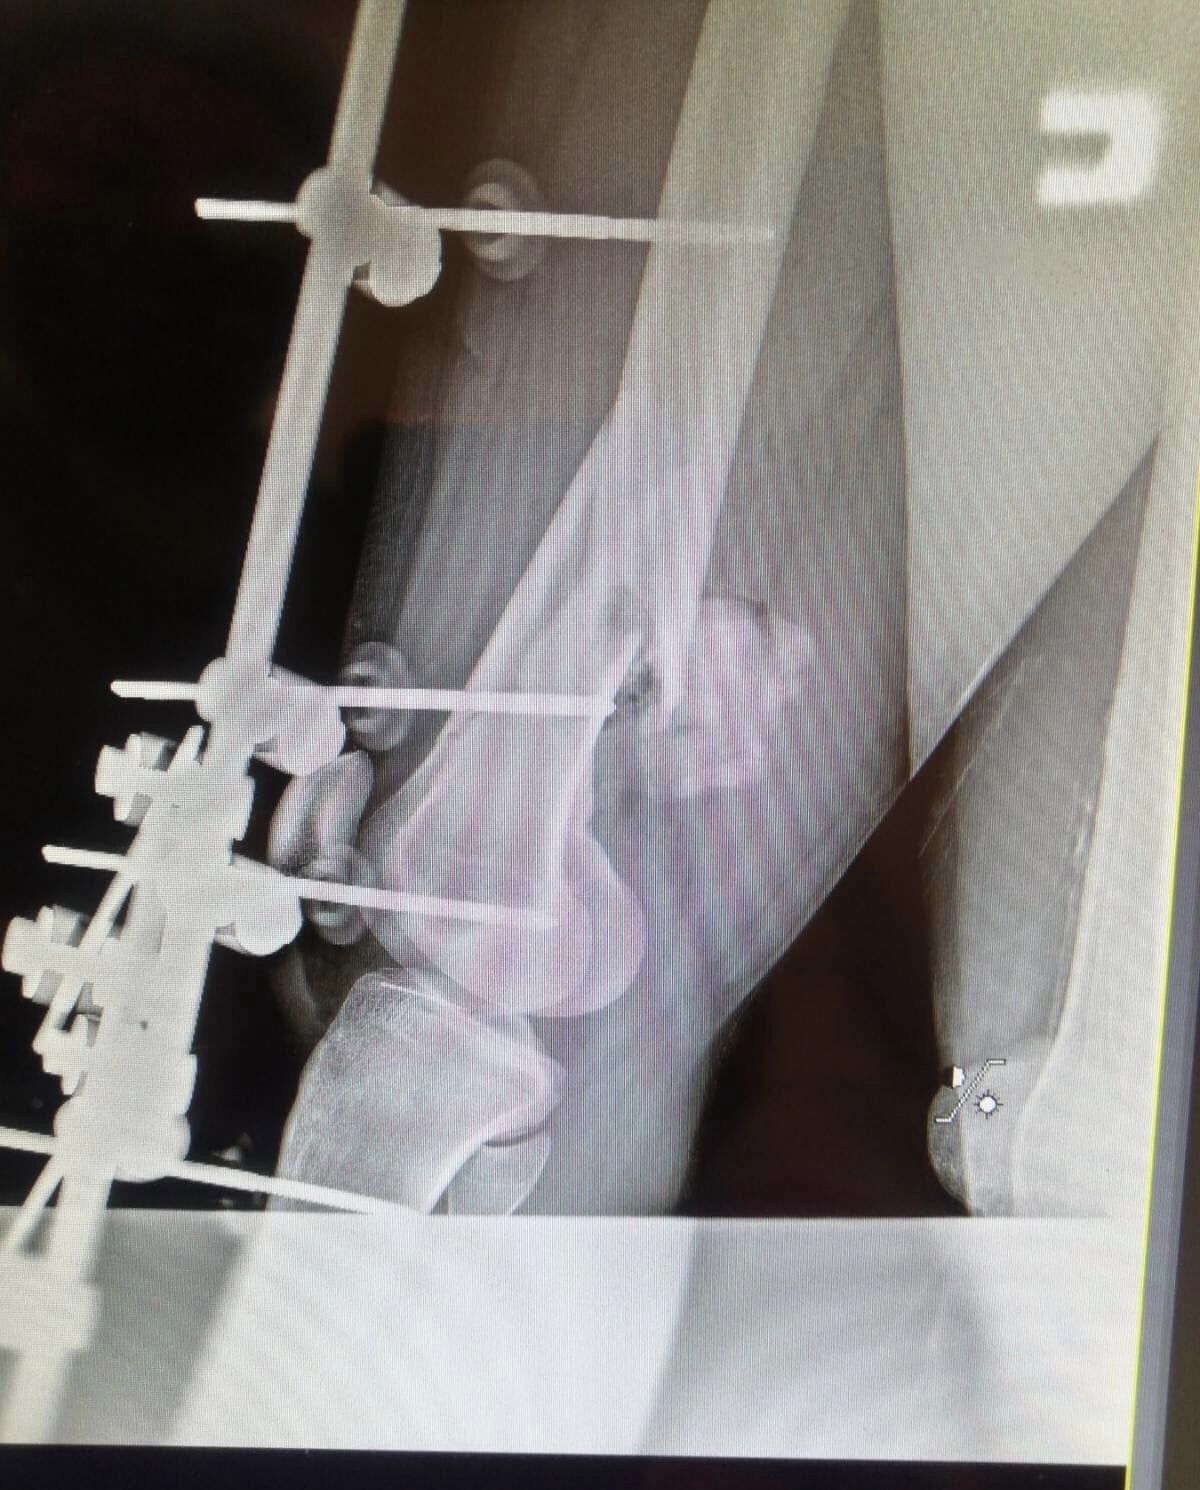

Опытные хирурги провели сложную операцию, вынули обломки и установили устройство для фиксации перелома. Боль сразу же покинула парня. Сейчас он восстанавливает силы и заживляет раны. Врачи беспокоятся о его здоровье, а семья окружила его заботой. Родные постоянно находится рядом.